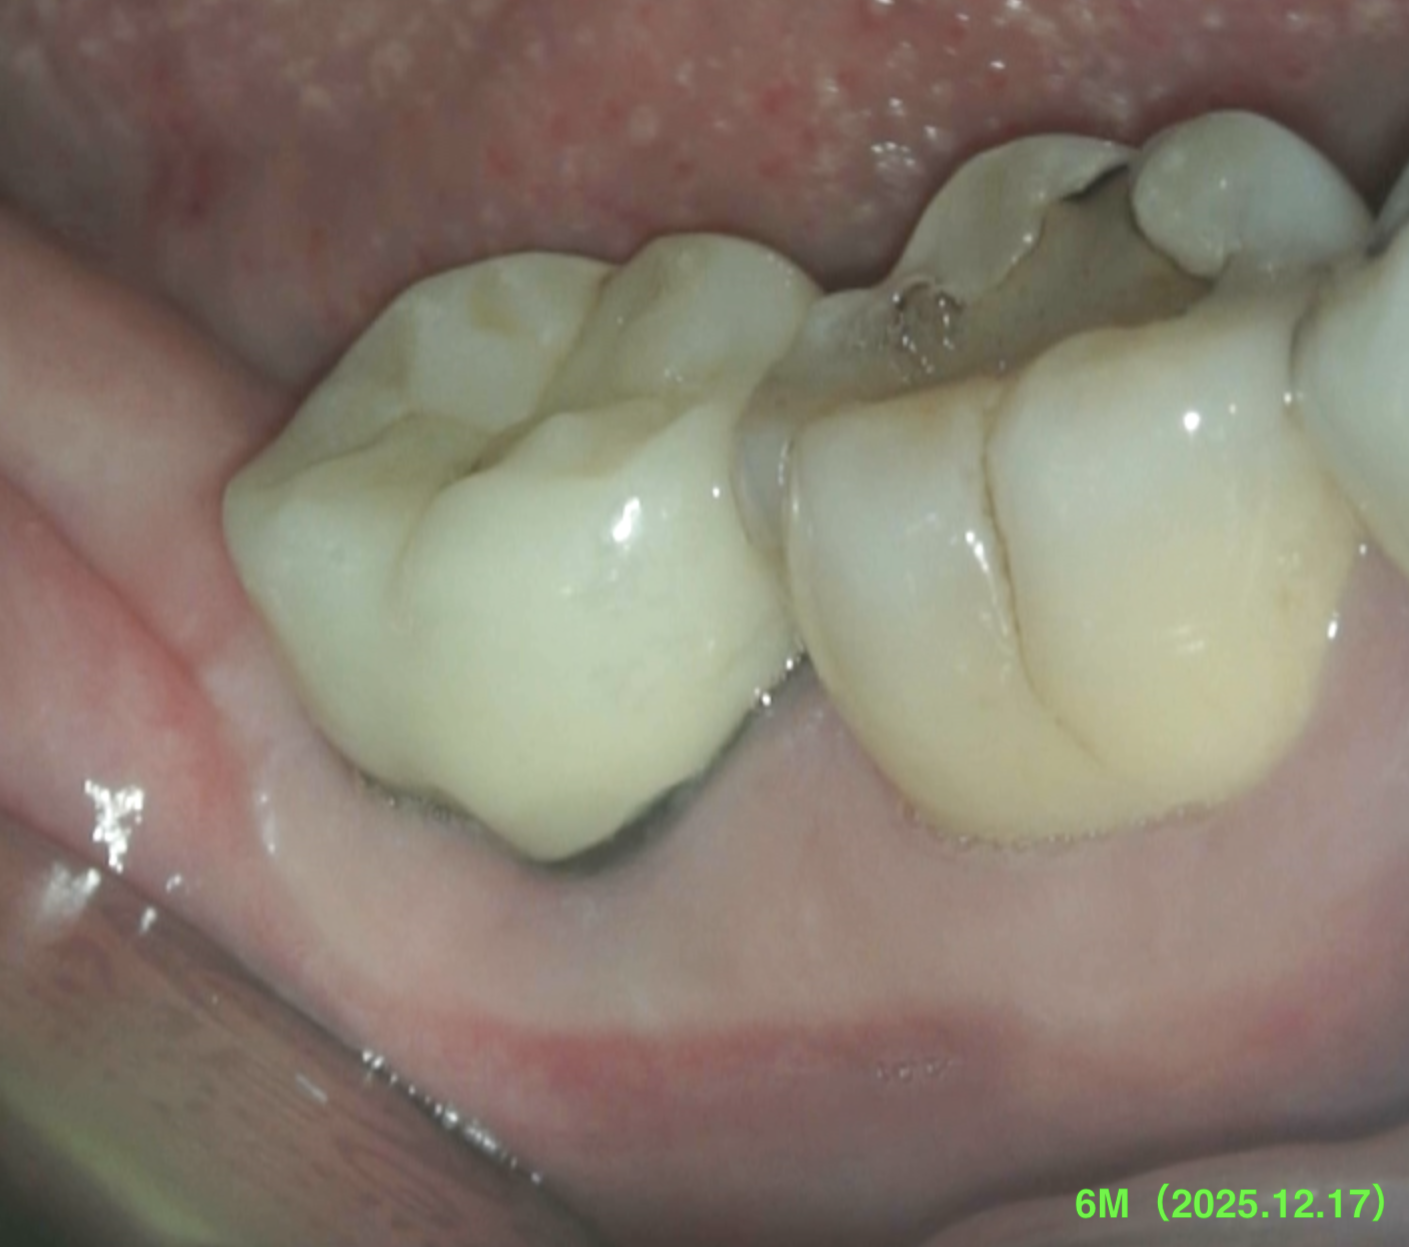

#31 Intentional Replantation 6M recall(2025.12.17)

すでに最終補綴が装着されている。

どの歯科医院に行っても歯が折れていると言われる…といわれたのに、だ。